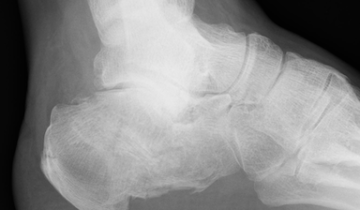

The Extremities

Differential Diagnosis